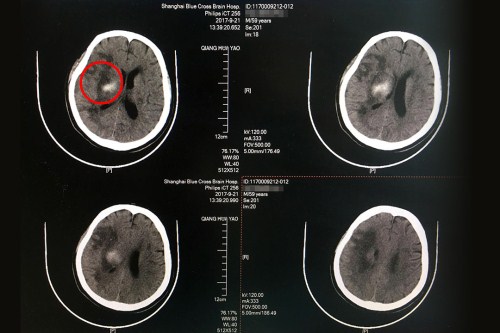

术后CT:右侧额颞枕叶梗塞伴右侧基底节区出血吸收中,皮层血供再通,较前好转